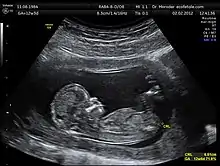

Знання з різних розділів акустики, широко використовуються, як для

діагностичної мети, так і задля організації терапевтичних процедур. У цьому разі, використовуються звукові сигнали у широкому діапазоні частот. Значну увагу у медичній акустиці приділяється також вивченню дії на організм людини звуків та вібрацій різної інтенсивності.